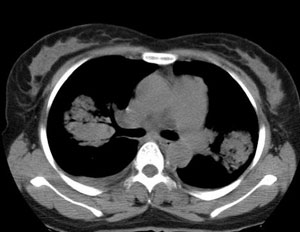

女性,30岁。

病史为胸痛20多天,无畏寒发热,无消瘦,无咳嗽咳痰。总之症状很逍遥。

临床以胸痛待查收住入院。

双肺野可见散在大小不等结节及肿块影,内密度不均匀,边缘部分清,部分欠清,纵隔未见明显肿大淋巴结.右侧胸腔少理积液.结合临床,考虑韦格肉芽肿可能吧,巨淋巴增生,结节病,特殊感染都要考虑.转移瘤临床不象.

本病例特点如下:

1.青年女性,以胸痛20多天就诊,无呼吸道及感染临床症状体征,无原发肿瘤病史;

2.肺ct表现为两肺多发大小不等结节影,大结节位于肺尖部,小结节多位于肺外带胸膜下,大结节内可见支气管充气征,周围可见月晕征(指在结节状或肉芽肿样病灶周围呈环形磨玻璃影),右肺门及腔静脉后可见小淋巴结,右侧胸腔内少量液体。

两肺散在分布大小不等的肿块及结节影,边缘毛糙,有分叶、毛刺,病灶密度不均匀,可见支气管充气相与空泡征。病变大多位于胸膜下,可见胸膜凹陷及胸腔积液。气管腔静脉间可见小结节影。